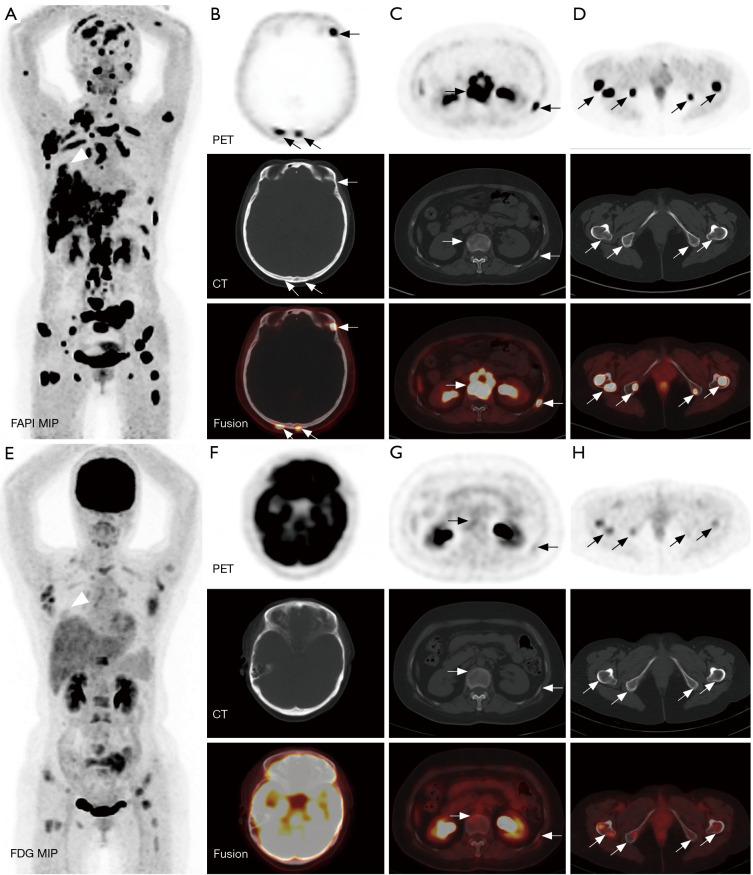

Bone metastases of lung cancer typically indicate disease progression and poor prognosis. Early and accurate detection is crucial for staging, treatment planning, and prognostic evaluation. This study aimed to compare the diagnostic value of gallium 68-labeled fibroblast-activation protein inhibitor-04 ([Ga]Ga-FAPI-04) and fluorine 18-labeled fluorodeoxyglucose ([F]FDG) positron-emission tomography/computed tomography (PET/CT) imaging in detecting bone metastases in lung cancer.

A retrospective analysis was conducted on patients with pathologically confirmed lung cancer and clinically suspected bone metastases. These patients underwent both [Ga]Ga-FAPI-04 and [F]FDG PET/CT imaging. Initially, all patient images were visually evaluated, and the diagnostic efficacy of the two imaging methods was compared at both the patient and lesion levels for detecting bone metastases from lung cancer. Additionally, a semi-quantitative analysis was performed to compare the optimal maximum standardized uptake value (SUVmax) threshold and diagnostic efficacy of the two examinations for diagnosing benign and malignant bone lesions.

A total of 25 lung cancer patients were included in the study, with nine confirmed cases and 133 lesions of bone metastases. At the patient level, there were no statistically significant differences in the detection rate, sensitivity, specificity, positive predictive value, negative predictive value, or accuracy between [Ga]Ga-FAPI-04 and [F]FDG PET/CT for identifying patients with bone metastases (P>0.05). At the lesion level, the detection rate, sensitivity, negative predictive value, and accuracy of [Ga]Ga-FAPI-04 PET/CT for detecting bone metastases were higher than those of [F]FDG PET/CT (81.37% 57.14%, 98.50% 69.17%, 88.24% 34.92%, 90.68% 70.81%), with statistically significant differences (P<0.01). The SUVmax of malignant bone lesions on both [Ga]Ga-FAPI-04 and [F]FDG PET/CT was significantly higher than those of benign bone lesions, with statistically significant differences (P<0.05). Moreover, the SUVmax of benign and malignant bone lesions on [Ga]Ga-FAPI-04 PET/CT was significantly higher than those on [F]FDG PET/CT, with statistically significant differences (P<0.01). In [Ga]Ga-FAPI-04 and [F]FDG PET/CT imaging, the area under the curves (AUCs) of SUVmax for diagnosing bone metastases were 0.856 and 0.724, respectively, with statistically significant differences (P<0.05); the optimal diagnostic thresholds were 5.38 and 3.77, respectively. The sensitivity, negative predictive value, and accuracy of SUVmax based on [Ga]Ga-FAPI-04 PET/CT for diagnosing lung cancer bone metastases were higher than those based on [F]FDG PET/CT (80.45% 65.26%, 46.49% 23.26%, 81.25% 67.29%), with statistically significant differences (P<0.05).

Compared to [F]FDG PET/CT, [Ga]Ga-FAPI-04 PET/CT significantly improves the detection rate of lung cancer bone metastases at the lesion level. Additionally, [Ga]Ga-FAPI-04 PET/CT offers superior image contrast and higher SUVmax, which also contribute to improving the accuracy of lung cancer bone metastasis diagnosis. This allows for more accurate staging of patients, enabling precise individualized treatment and improving patient prognosis.